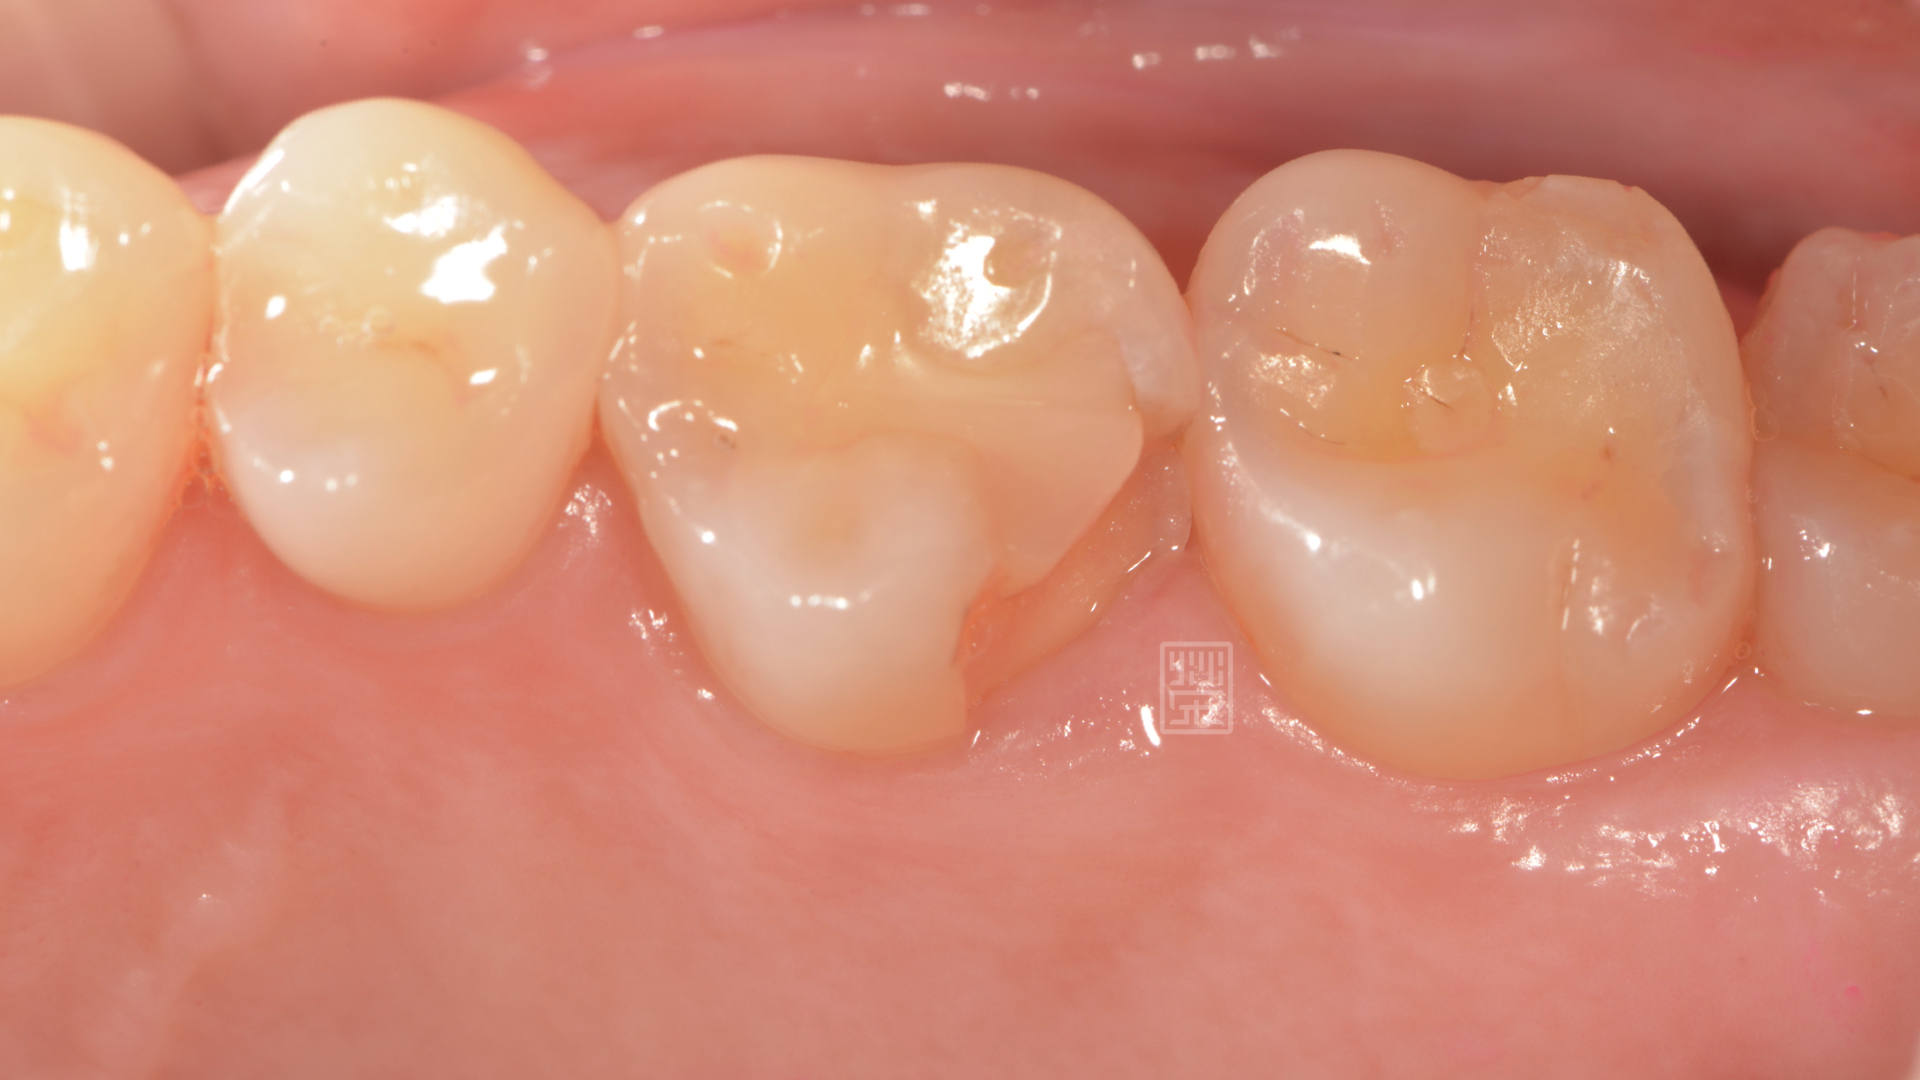

牙齒邊緣破裂